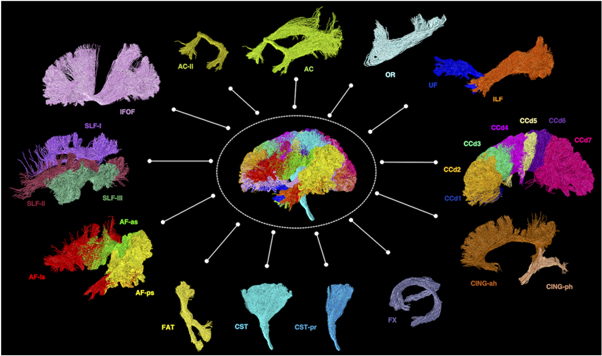

Using dMRI tractography, streamline trajectories can be generated that seem to follow the path of known WM tracts (figure 6). Importantly though, tractography does not reconstruct actual WM fibres or axons but only streamlines (or curves in 3D space) that are mathematical representations that delineate possible WM tracts—a crucial concept that has been misused quite frequently for applications in the field (Jones et al 2013, Jeurissen et al 2019).

Figure 6. Examples of diffusion MRI tractography of known major white matter tracts in the human brain 12 . Material acronyms: AC (anterior commissure), AC-ll (anterior commissure, the lateral (temporal) limb component), AF-as (arcuate fasciculus, the anterior indirect segment), AF-ls (arcuate fasciculus, the long direct segment), AF-ps (arcuate fasciculus, the posterior indirect segment), CCd1-7 (corpus callosum, segments 1-7), CING-ah (cingulum, the anterior horizontal segment), CING-ph (cingulum, the parahippocampal segment), CST (corticospinal tract), CST-pr (corticospinal tract, the peri-Rolandic component), FAT (frontal aslant tract), FX (fornix), IFOF (inferior fronto-occipital fasciculus), ILF (inferior longitudinal fasciculus), OR (optic radiation), SLF-I-III (superior longitudinal fasciculus, components I–III), UF (uncinate fasciculus).